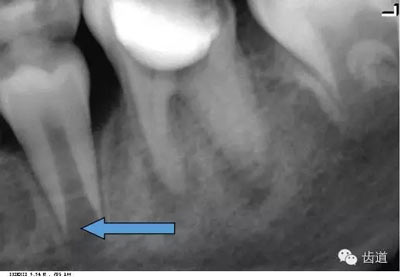

牙頸部Burnout征象:有時因投照技術(shù)問題而造成牙頸部近中或遠(yuǎn)中呈低密度影像,位于牙釉質(zhì)和牙槽嵴頂之間。